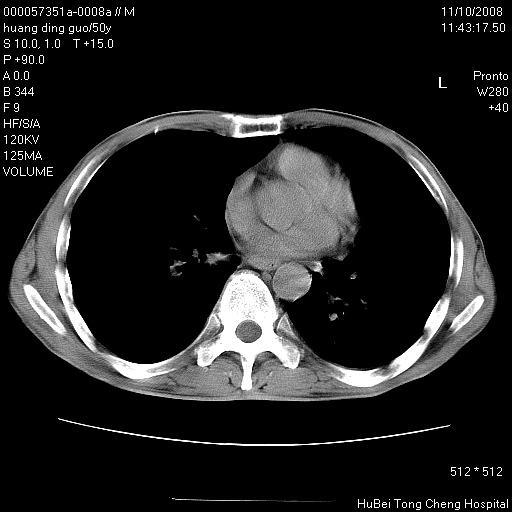

患者 男,50岁。左侧腰背部疼痛3月余,伴消瘦。平素健康,无传染病史。

胸部ct轴位平扫(层厚10mm,螺距1.5,重建间隔10mm),图像如下:

左肺下叶背段有一厚壁空洞,外壁呈锯齿状伴毛刺改变。空洞相邻胸膜有牵拉改变。左肺下叶血管支气管束不规则增粗,小叶间隔增厚。胸椎骨质破坏。考虑左肺下叶周围型肺癌伴左肺下叶癌性淋巴管炎、胸椎转移。

左肺下叶背段有一厚壁空洞,外壁呈锯齿状伴毛刺改变。空洞相邻胸膜有牵拉改变。左肺下叶血管支气管束不规则增粗,小叶间隔增厚。胸椎骨质破坏。考虑左肺下叶周围型肺癌伴阻塞性肺炎、胸椎转移。其他待排

左肺下叶背段有一厚壁空洞,内壁不规则,外壁呈锯齿状伴毛刺改变。空洞相邻胸膜有牵拉改变。周围呈絮状炎性改变,左肺下叶血管支气管束不规则增粗,小叶间隔增厚。胸椎骨质破坏。考虑左肺下叶周围型肺癌伴左肺下叶阻塞性肺炎、胸椎转移。